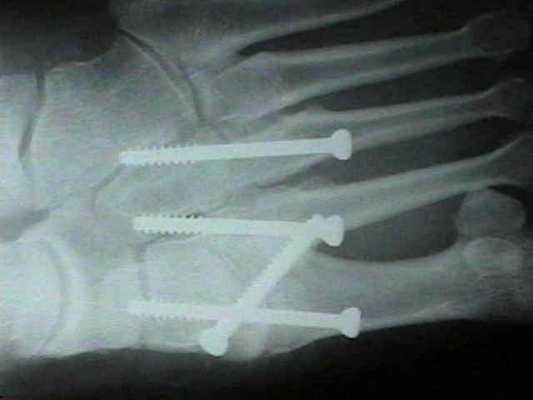

Даже при изолированном связочном повреждении со значительной нестабильностью рекомендуется артродез 1-2-3 предплюсне-плюсневых суставов. Данный вид лечения характеризуется меньшим количеством осложнений (таких как посттравматический артроз и миграция металлофиксаторов) чем открытая репозиция с внутренней фиксацией. После операции рекомендуется ношение циркулярной гипсовой иммобилизации 6 недель, ходьба без нагрузки. Постепенное увеличение осевой нагрузки с 6 по 12 неделю.

При прогрессивном коллапсе сводов стопы, хронической нестабильности, прогрессивном наружном смещении переднего отдела стопы рекомендуется артродез всего суставного комплекса Лисфранка. Существует много вариантов выполнения данного вмешательства, с использованием спиц, винтов, скоб и пластин, в зависимости от оснащённости операционной и предпочтений хирурга. После операции потребуется 6 недель гипсовой иммобилизации, полную нагрузку можно давать не ранее 10 недели.

В ряде случаев целесообразно применить смесь хирургических техник. Если рассматривать весь сустав Лисфранка разбив на внутренний, центральный и наружный отделы, то его внутренний (1) и латеральный (4-5) отделы подвижны, хотя и с малой амплитудой, а центральный (2-3) практически не подвижен. По этой причине в хирургической практике часто используется неполный артродез, то есть выполняют артродез 2-3 предплюсне-плюсневых суставов а 1,4,5 временно фиксируют спицами.

Это позволяет сохранить нормальную биомеханику стопы и предотвратить раннее развитие артроза в смежных суставах которое характерно для полного артродеза.

После осмотра в отделении ортопедии №2 ГКБ №13 принято решение о проведении операции - открытому устранению вывиха, артродезе 1-2-3 плюсне-клиновидных суставов, 1 межклиновидного сустава при помощи винтов и пластины, трансартикулярной фиксации спицами 4-5 плюсне-клиновидных суставов.

После восстановления 2 луча выполняем артродез межклиновидного сустава и 1 плюсне-клиновидного сустава. Учитывая что основная нагрузка ложится на 1 луч, дополнительно стабилизируем его при помощи пластины.